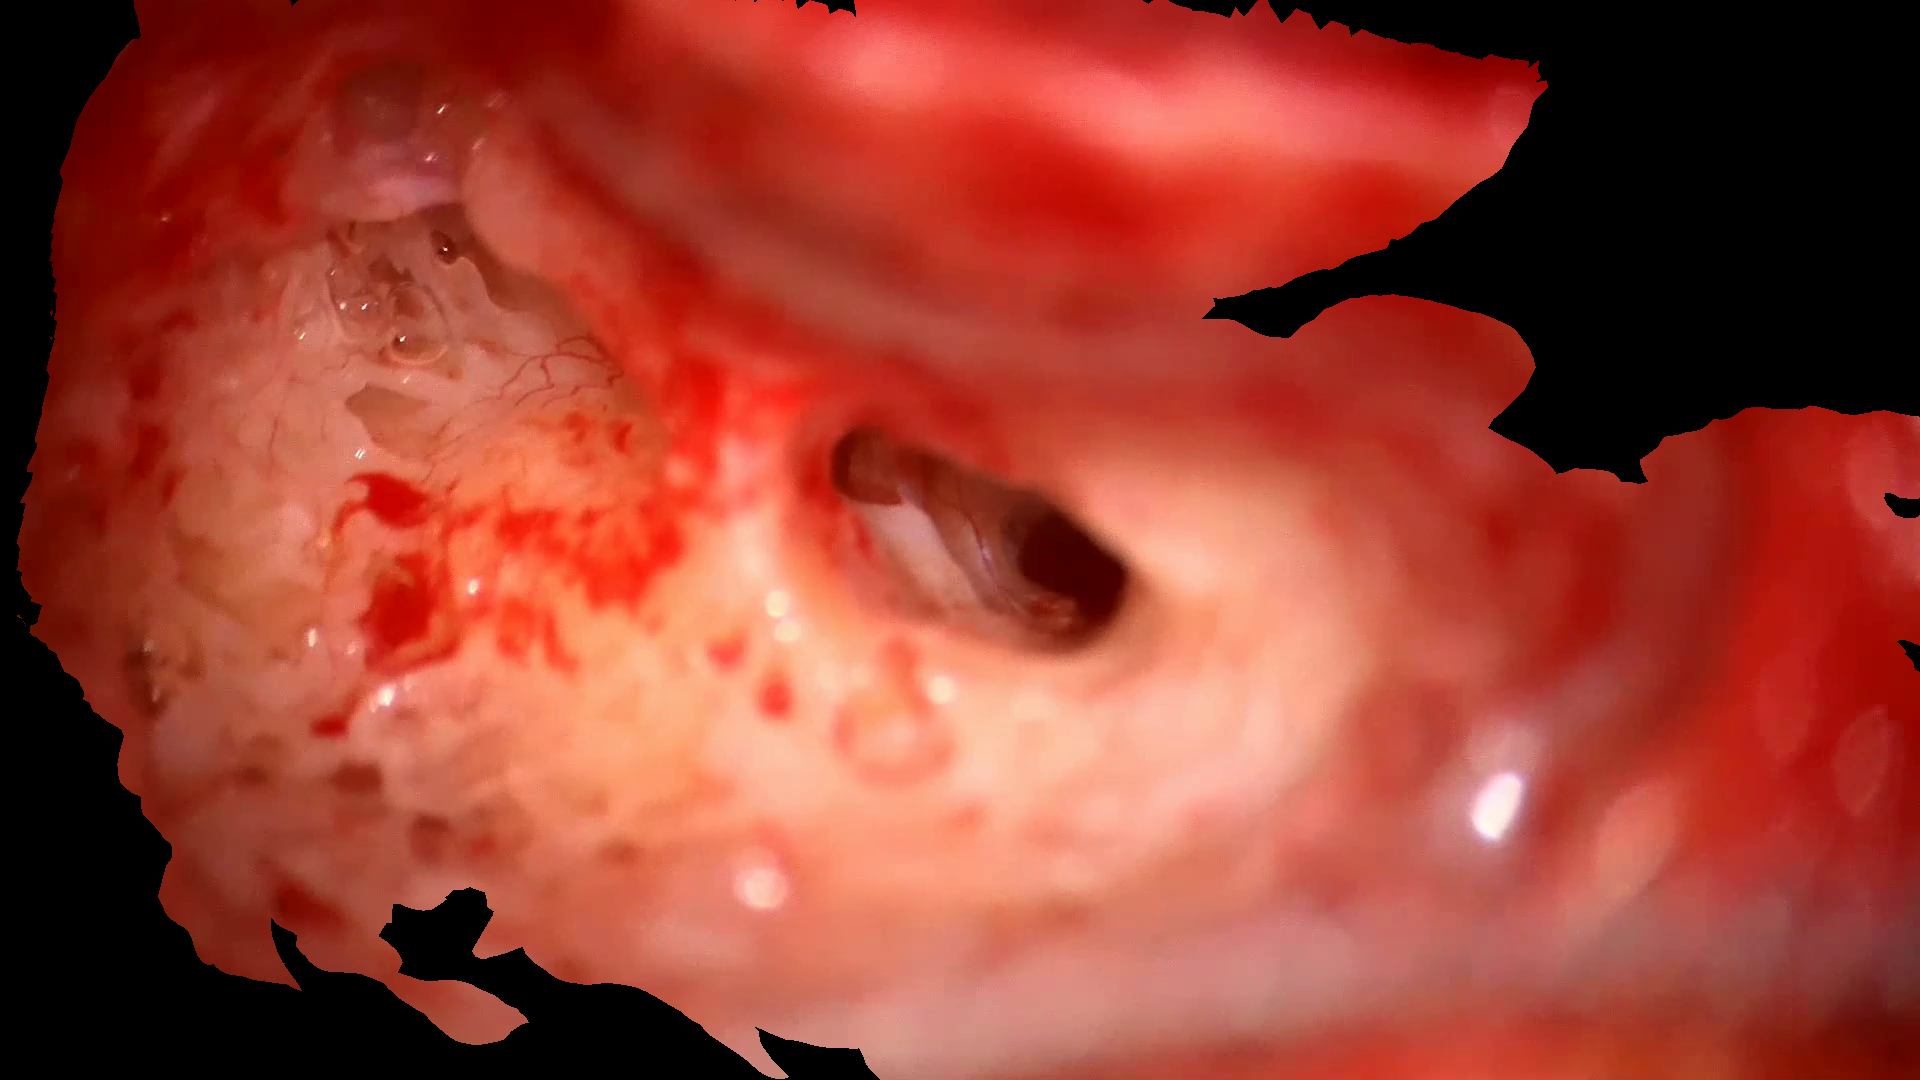

A single frame I𝐼Iitalic_I is selected from the recorded video that presents a clear microscopy view, free from any occlusion either caused by the surgeon’s hands or the surgical tools. Given a preset camera intrinsic matrix, we manually aligned the surface with the selected frame in our customized open-source software Vision6D[5] to obtain an accurate initial pose of the reconstructed CT mesh, as shown in Fig. 2. The corresponding features between the microscopy view and the CT mesh are circled in matching colors.

Refer to caption

(a) Selected microscope view

(b) Register CT mesh to the microscope view

Figure 2: Register CT mesh to the microscope view.